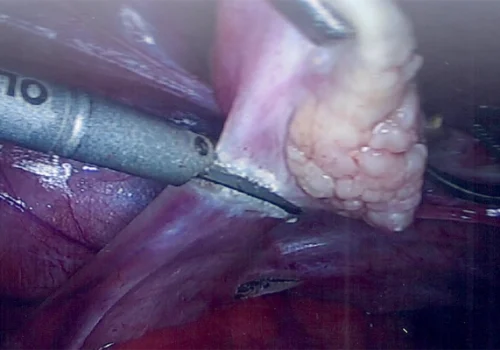

Florid Adenomyosis - Total Laparoscopic Hysterectomy

The pathology specimen revealed florid adenomyosis.